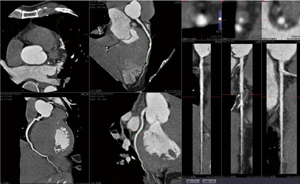

3D画像の活用としては、心臓CTの冠動脈解析を中心に、冠動脈バイパス術後評価、下肢動静脈の描出、アブレーション治療における左房形態などの術前評価などが行われている。VGRクライアントは、カテ室にも設置され、PCI手技前のカンファレンスで冠動脈CTのVRやCPRによる確認や、術中にはカテ室内のモニタに画像を表示して手技を支援する。

現状では、冠動脈解析は放射線部から提供される再構成画像が高い完成度があるため、循環器内科医が3Dを作成する機会は少ないが、PCIの手技前に石灰化やプラークの把握や解析のために、ziostation2を使っているという。貞松部長は、「ziostation2によって高精細で精度の高い冠動脈解析のデータが提供されるようになりました。新病院ではネットワークでのWSの利用に制限がなくなったので、見たい時に場所を選ばず3Dの閲覧や作成が可能で機動性が良くなりました。ziostation2は機能が豊富で使いこなすというところまでいっていませんが、今後、機能を把握してフルに活用していきたい」と期待を述べている。

■ziostation2を用いた臨床画像

循環器内科でのCT冠動脈解析を用いた |